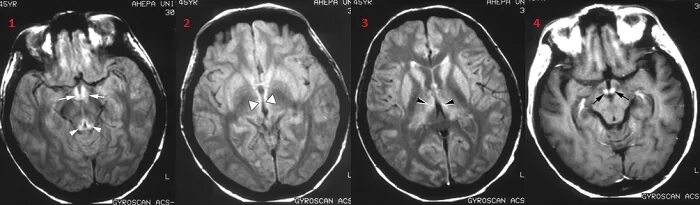

Синдром гайе